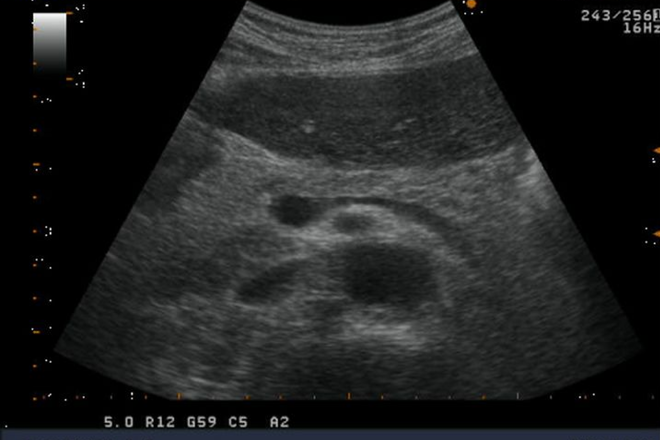

Pancreatitis crónica: en estadios avanzados es fácil su reconocimiento,  por presencia de calcificaciones intra ductales,, dilatación del conducto pancreático principal, lesiones quísticas o sólidas cercanas al conducto pancreático, atrofia glandular,  y parénquima heterogéneo.  En el grado moderado la ecogenecidad es homogénea por fibrosis hiperecogénica. Así como infiltración grasa.